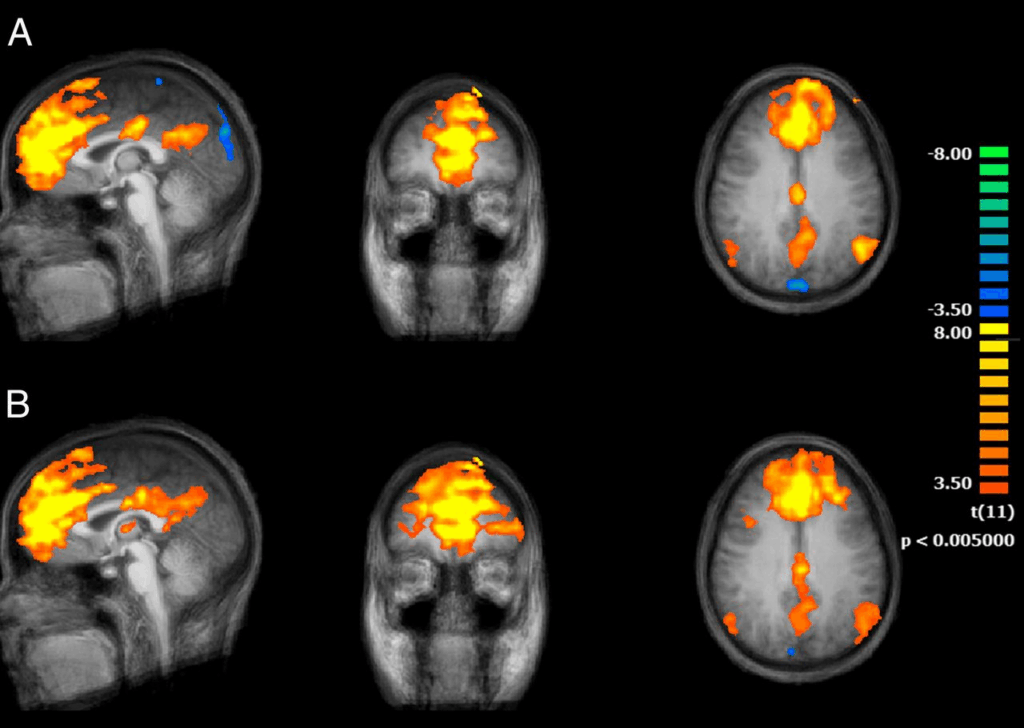

A privação de sono ativa de forma exagerada a amígdala, parte do cérebro ligada às emoções. Resultado: mais ansiedade, maior irritabilidade e risco aumentado de depressão (Yoo et al., Current Biology, 2007).